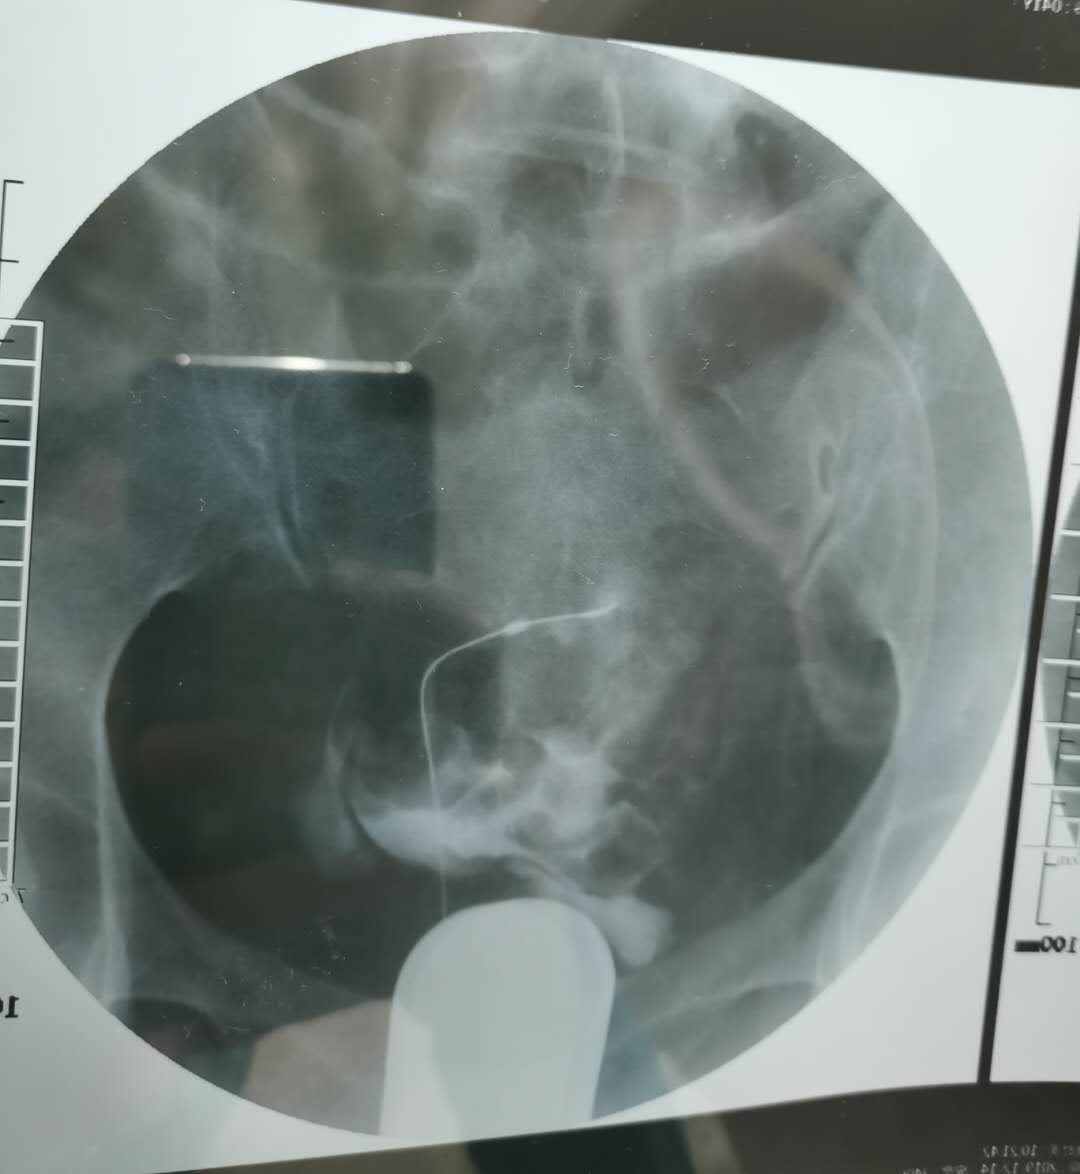

我这个是做了输卵管介入手术,请问输卵管是通了